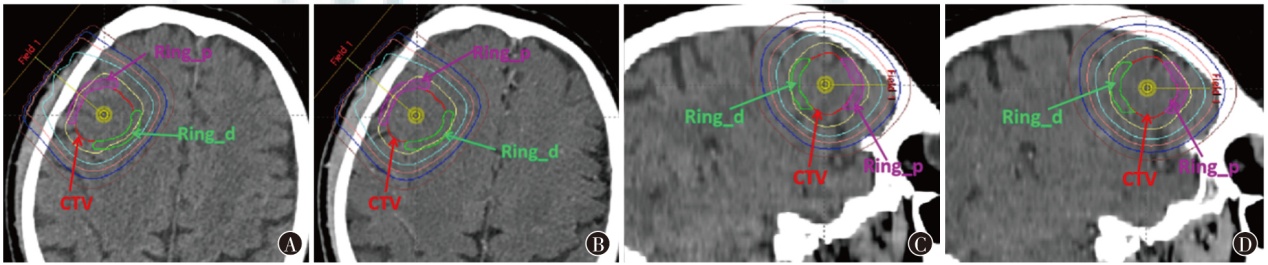

目的系统评估双能CT(DECT)中虚拟平扫(VNC)图像与真实平扫(TNC)图像在CT值上的差异,并验证VNC图像在光子、质子放疗计划剂量计算中替代TNC图像的可行性。方法回顾性分析2022年2月至2023年5月于百度开云体育app附属肿瘤医院接受DECT检查的40例实体瘤患者(头颅20例,胸、腹部各10例)的影像数据。对VNC与TNC图像逐层配准,并比较不同解剖结构的CT值差异,采用Pearson相关分析评估VNC与TNC图像中不同解剖结构CT值的相关性。对差异显著的结构采用最小二乘法建立回归模型(TNC=βVNC+α)。在Eclipse 15.5放疗计划系统中分别设计基于TNC图像与VNC图像的光子与质子放疗计划,以及基于回归模型校正后VNC图像的质子放疗计划,评估两种图像放疗计划的剂量差异。为评估临床靶区(CTV)邻近区域的剂量变化,于CTV所在轴向最大层面分别向前(头侧)和向后(足侧)方向构建厚度为2 mm的环形参照结构,分别命名为Ring_p与Ring_d。结果VNC与TNC图像的CT值差异主要集中于骨性结构,20例颅脑肿瘤患者的颅骨CT值差异为(409.07±53.38)HU(t=13.88,P<0.001),10例胸部和10例腹部肿瘤患者的脊椎骨CT值差异为(118.66±20.90)HU(t=10.43,P<0.001)。TNC与VNC图像的颅骨(r=0.98,P<0.001)和脊椎骨(r=0.99,P<0.001)CT值均高度相关,分别建立回归模型为:TNC=1.859×VNC+33.896和TNC=1.827×VNC+5.491。基于TNC图像与VNC图像设计的光子放疗计划中,CTV的Dmean分别为(60.00±0.00)与(60.00±0.00)Gy,Ring_p的Dmean分别为(61.17±1.69)与(61.01±1.67)Gy,Ring_d的Dmean分别为(55.26±2.06)与(55.20±1.94)Gy,两组间Dmean的相对剂量差分别为0(t<0.01,P>0.999)、0.33%(t=0.30,P=0.766)和0.19%(t=0.07,P=0.947),差异均无统计学意义。基于TNC图像与VNC图像设计的质子放疗计划中,CTV的Dmean分别为(61.73±0.32)与(61.67±0.26)Gy(RBE),Ring_p的Dmean分别为(61.19±0.44)与(60.53±1.22)Gy(RBE),Ring_d的Dmean分别为(60.97±0.67)与(59.80±4.26)Gy(RBE),两组间Dmean的相对剂量差分别为0.24%(t=0.63,P=0.530)、1.80%(t=1.45,P=0.156)、3.56%(t=2.26,P=0.030),其中Ring_d区域差异有统计学意义。基于校正后VNC图像设计的质子放疗计划中,CTV的Dmean为(61.75±0.32)Gy(RBE),Ring_p的Dmean为(61.43±0.71)Gy(RBE),Ring_d的Dmean为(59.96±2.80)Gy(RBE),基于TNC与校正后VNC图像间Dmean的相对剂量差分别为0.16%(t=0.19,P=0.850)、0.76%(t=1.32,P=0.196)和2.22%(t=1.93,P=0.061),差异均无统计学意义。结论DECT中VNC与TNC图像的CT值差异主要存在于骨性结构,尤其是颅骨和脊椎骨。对于颅脑肿瘤患者,VNC图像可以直接用于光子放疗计划;而在质子放疗中,VNC图像经回归模型校正后,可有效替代TNC图像用于放疗计划剂量计算。